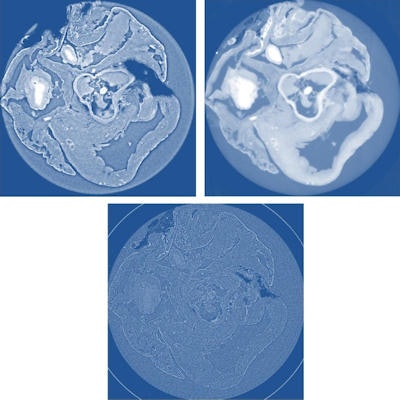

Using a tumor excised from a mouse model and a healthy rat heart, the researchers implemented the three techniques using the ID19 beamline at the ESRF with monochromatic 17.6 keV and 19 keV x-ray beams, respectively. A CCD detector with effective pixel sizes of 3-8 mm was used. In each scan, the samples were rotated through 360° and approximately 1,500 projections were acquired (Journal of Applied Physics, 21 October, 2014, Vol. 116:15, pp. 154903)

Analysis of the resulting scans revealed that each technique has advantages and limitations, qualitatively and quantitatively, as well as practically.

Examining image quality, significantly higher contrast-to-noise ratios (CNR) were observed for XGI scans, corresponding to more precise measurements of material density. For instance, in soft tissue in the heart, XGI gave a CNR of 55 compared with a range of 9-25 for the propagation-based techniques. For the same tissue, CNR values obtained from absorption scans constructed with the same data were less than one.

In a contrasting finding, HT and SDPR produced images with significantly better spatial resolution. Resolution for the two ranged from 8 mm to 12 mm, compared with 25 mm for XGI. The three techniques also varied in complexity. For example, data processing for SDPR, as well as acquisition, is the simplest of the three. Consequently, the researchers concluded that all three techniques are complementary tools that should be chosen according to the application.